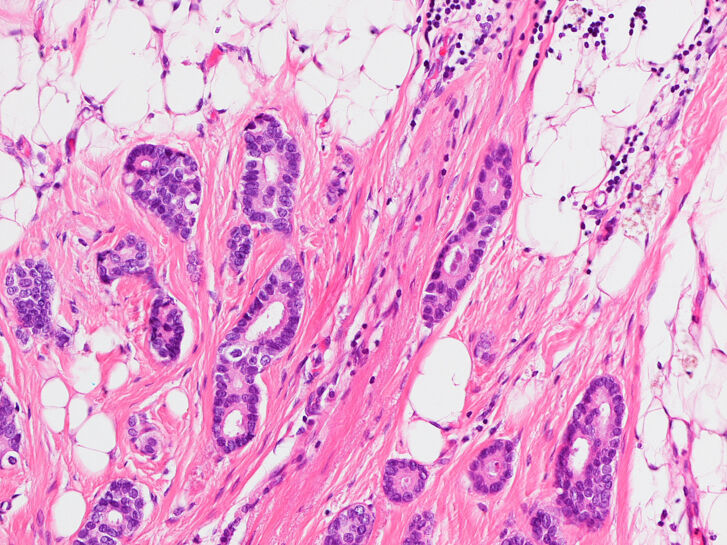

Die 15 Ärztinnen und Ärzte und ca 50 Mitarbeiterinnen und Mitarbeiter des medizinisch technischen und administrativen Dienstes unseres Instituts führen zytologische, histologische, immunhistologische, molekularbiologische, medizinisch-mikrobiologische, infektionsserologische und krankenhaushygienische Untersuchungen sowie Autopsien durch. Dieses Service steht allen Landeskrankenhäusern, Krankenanstalten, ärztlichen Praxen in Vorarlberg und anderen Bundesländern sowie Einsendern aus dem Ausland zur Verfügung.

Das technologische Armamentarium reicht dabei von der Mikroskopie über die Immunologie und Biochemie bis zur Proteomanalyse und Molekulargenetik.